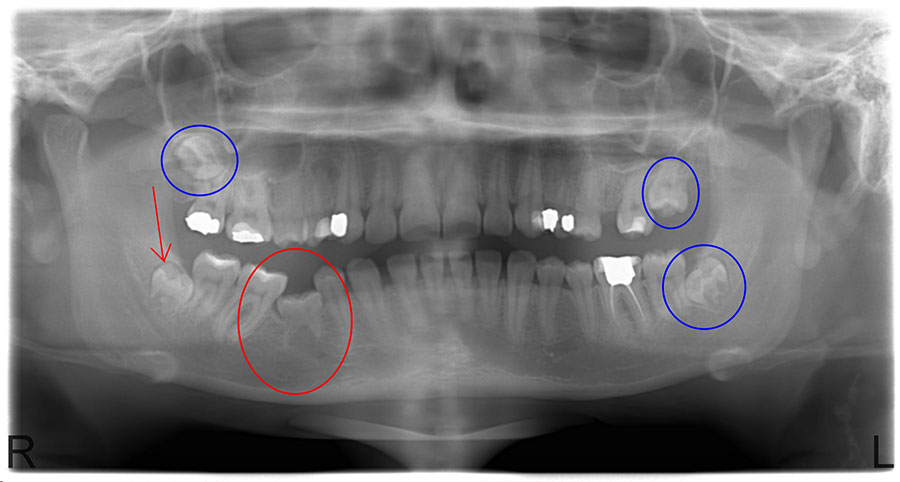

Görsel Notu: Alt ve üst çenede dört adet gömülü diş göze çarpıyor. Özellikle alt çenedekilerin artık kemikten dışarı çıkmakta olduklarına dikkat ediniz.

Görsel Notu: Sağ alt gömülü azı dişinin (kırmızı ok), ön azı (premolar) diş çıkışını (kırmızı daire) engelleyecek şekilde dişleri itmesi mümkündür. Diğer gömülü dişler de (mavi daireler) komşu diş köklerine bası yapmaktalar.